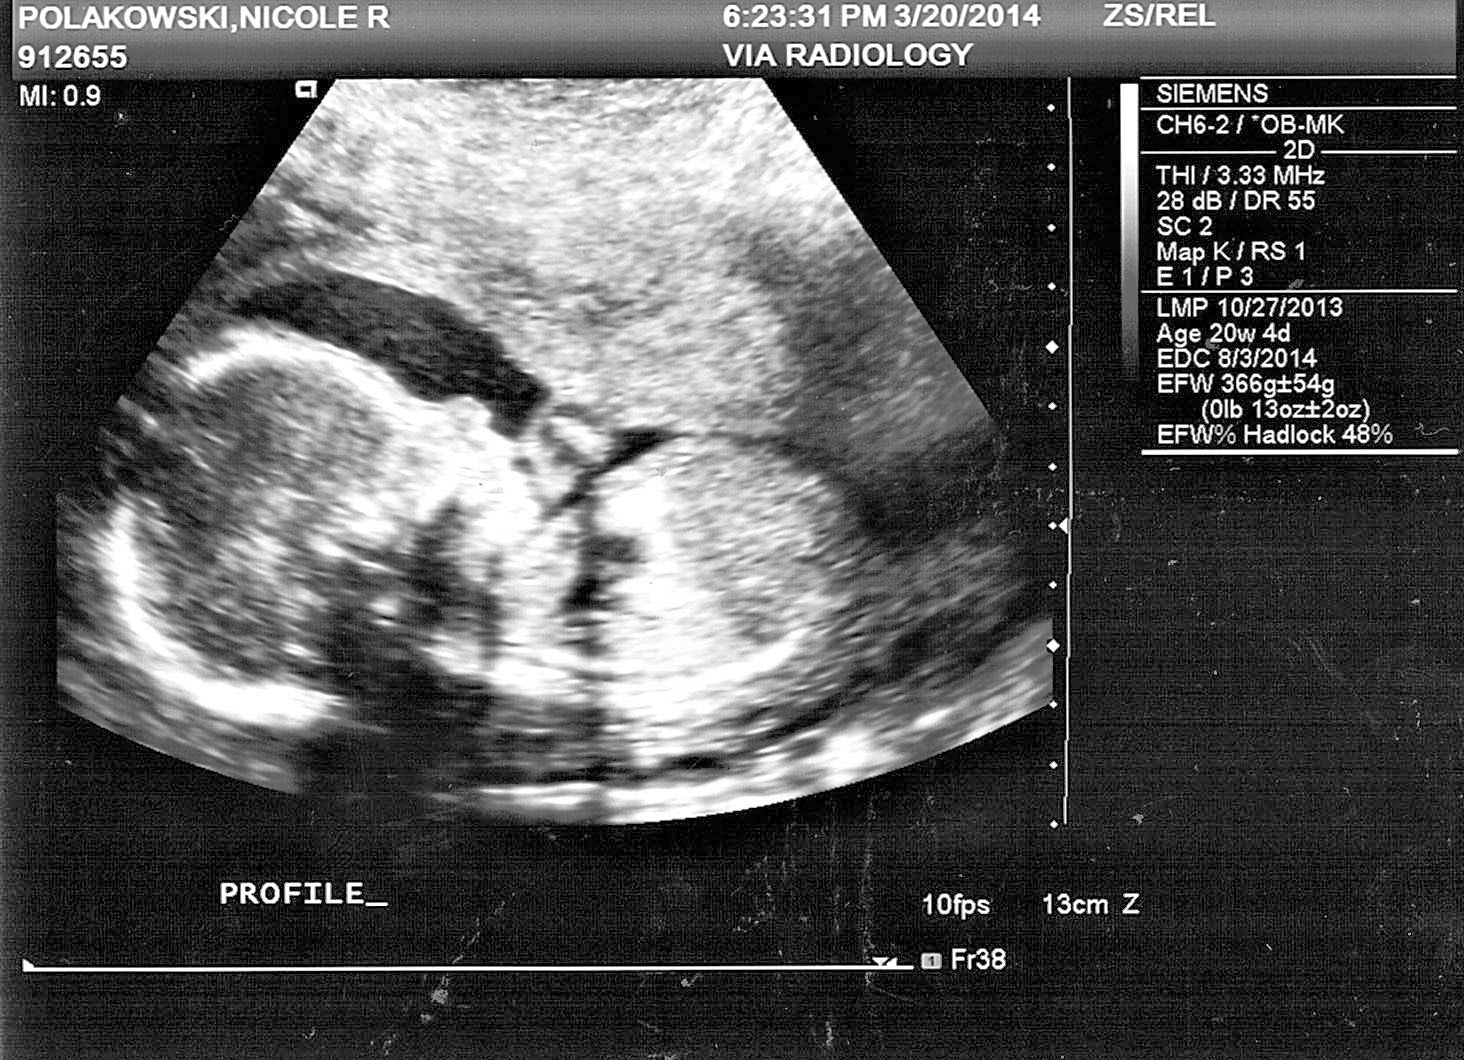

From nicolakowski.blogspot.com

20 Week Anatomy Ultrasound How Long Does An Anatomy Scan Ultrasound Take Find out what measurements are taken,. It can detect some birth defects, but it's not. the anatomy ultrasound is a level 2 ultrasound that examines your baby's heart, brain, spine, and other systems. an anatomy scan is a detailed ultrasound that checks your baby's development at around 20 weeks. How Long Does An Anatomy Scan Ultrasound Take.